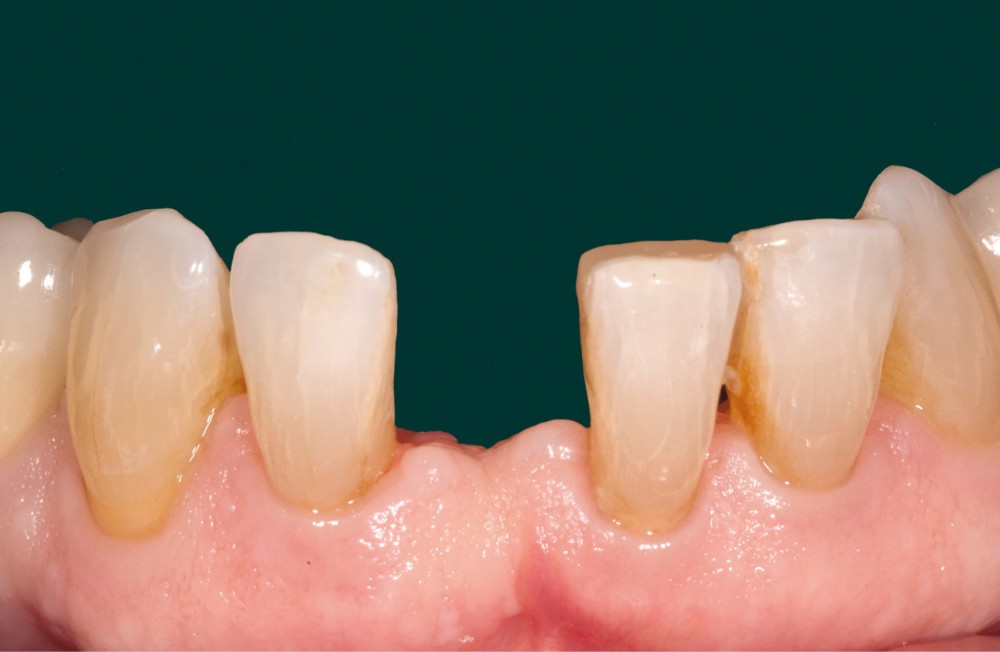

La patiente est venue consulter à la suite du descellement de la pièce zircone qui, agissant comme une attelle de contention, subissait des contraintes de torsion importantes. Malgré plusieurs tentatives infructueuses de remise en place (fig. 3), nous avons proposé à la patiente, compte tenu des rapports occlusaux favorables, de réaliser un bridge cantilever en disilicate de lithium (IPS e.max, Ivoclar Vivadent) plus apte au collage [1]. Cette thérapeutique est un choix biologique et biomécanique séduisant, validé par la littérature scientifiquement [2].